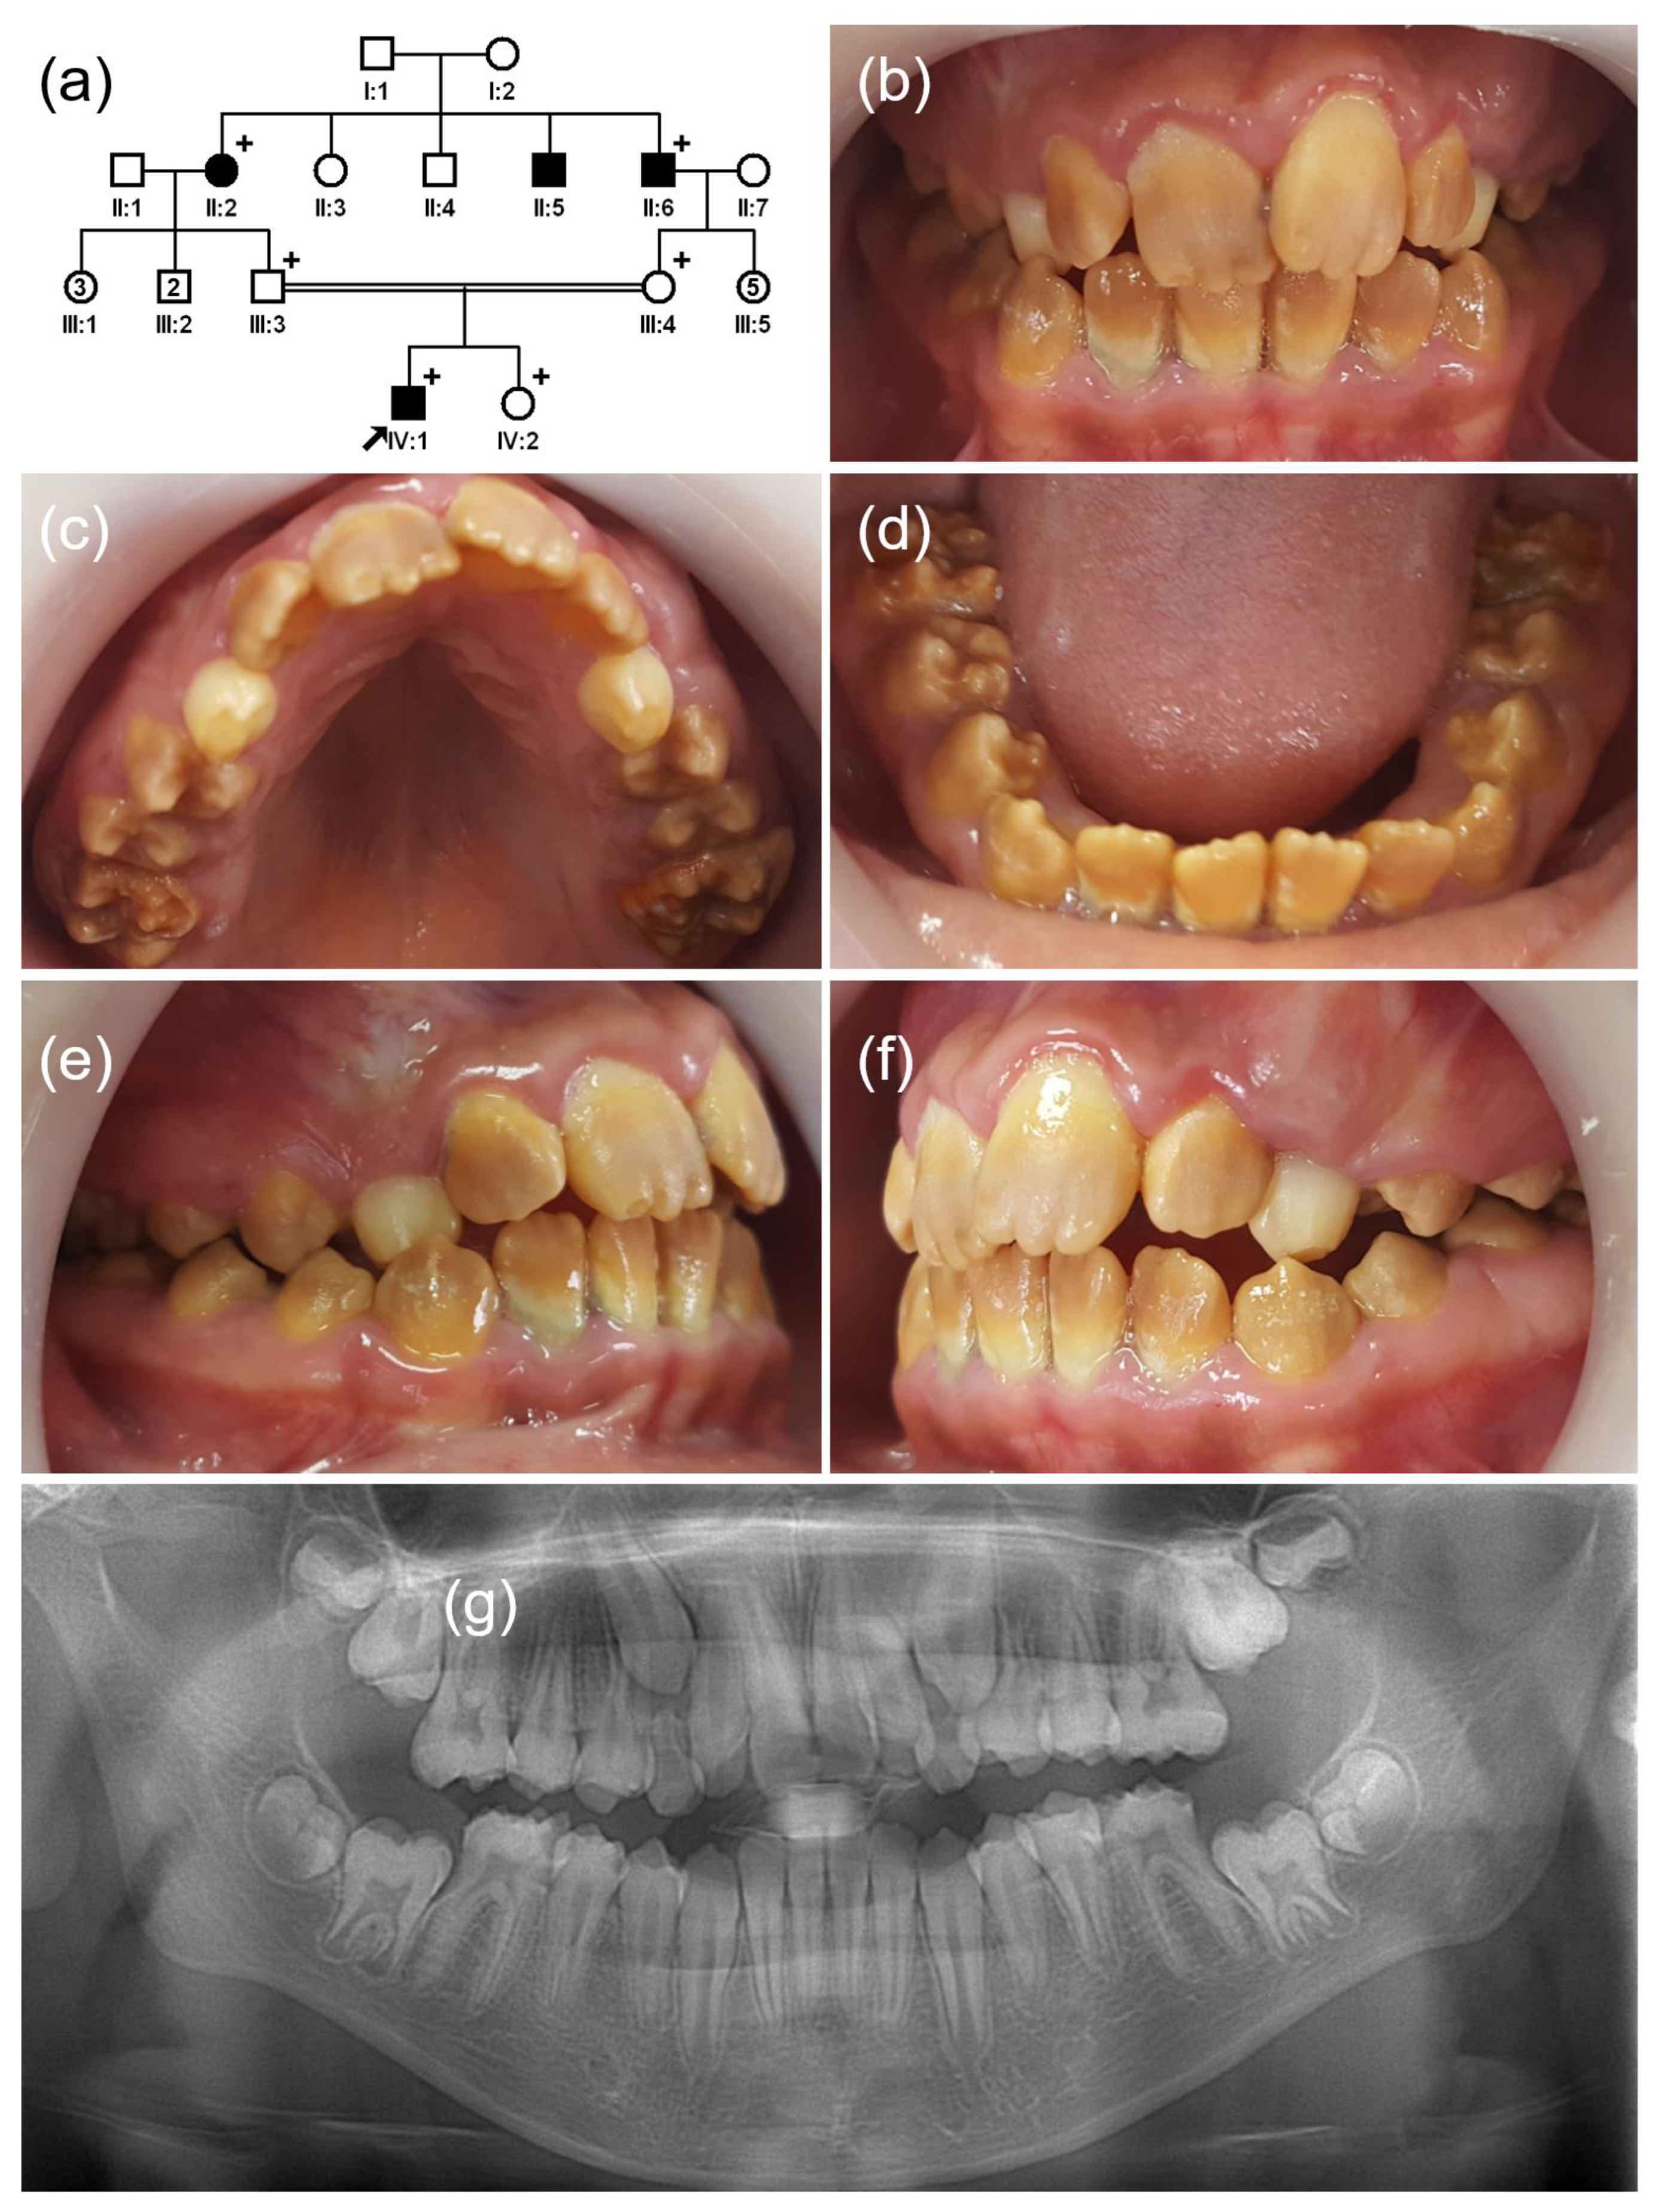

3.1. Family 1